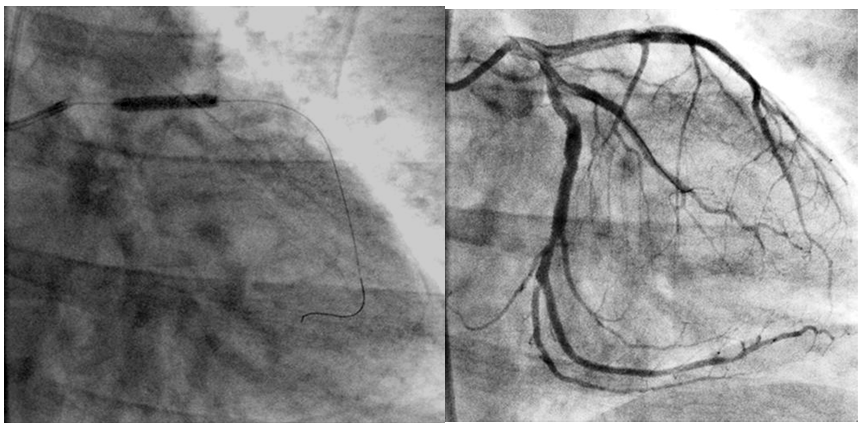

There was significant improvement in the TIMI flow grade after PPCI but there was no significant difference between two groups; TIMI flow grade 0 improved from 86.7 to 1.7%, TIMI grade I from 6.7% to 1.7%, TIMI grade II from 3.3% to 6.7% and TIMI grade III from 0% to 86.7%. Figure 1-3 of patient of group B.

Figure 1 Shows ECG and coronary angiography at time of presentation.

Figure 2 Shows stent implantation after thrombus aspiration and TIMI flow grade III.